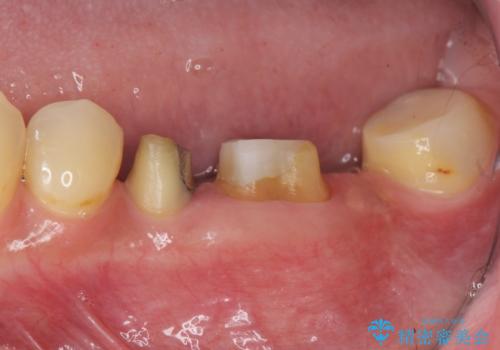

[メタルフリー] 虫歯・銀歯だらけの口腔内を全顎治療

![[メタルフリー] 虫歯・銀歯だらけの口腔内を全顎治療の症例 治療前](https://seimitsushinbi.jp/wp/wp-content/uploads/2025/03/e26a9887bc6905a2f0f51f5772b5ac9c-500x350.jpg?v=1741918285)

![[メタルフリー] 虫歯・銀歯だらけの口腔内を全顎治療の症例 治療後](https://seimitsushinbi.jp/wp/wp-content/uploads/2025/03/530cf6cca6451bc106a9fb69dd58908a-500x350.jpg?v=1741918343)